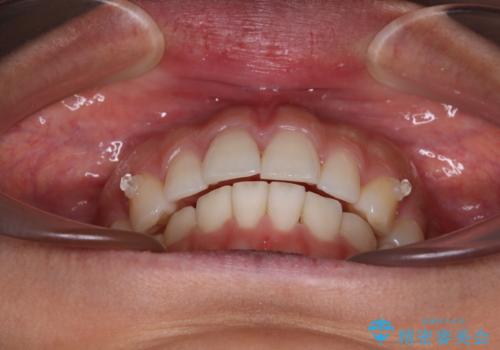

【モニター】突出した前歯 補助装置を併用したインビザライン矯正

- 上下前歯が非接触となり、前方に突出していることを気にして来院された患者様です。

咬合力が強く、全体的に歯がすり減っているため、インビザライン単独での上顎歯列移動は困難と判断し、補助装置により上顎歯列を後方移動させ、その後インビザラインにて仕上げていくこととしました。

補助装置なしでも改善できる可能性はありましたが、補助装置で確実性を上げ、短期間できっちりと仕上げることができました。